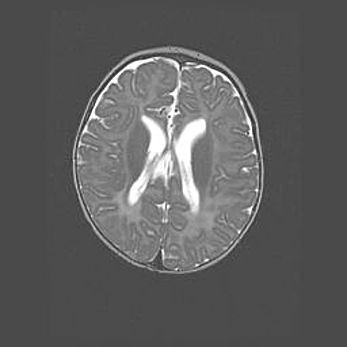

Множественные мелкие кисты перивентрикулярной области.

Киста прозрачной перегородки.

Возраст: 28 дней

Вес: 2400 г

Пол: женский

Окружность головы: 33 см

Срок гестации: 34 недели

Перивентрикулярная киста – это полостное образование в околожелудочковых областях белового вещества головного мозга. С морфологической точки зрения – это мелкоочаговая зона коагуляционного некроза, возникшая после инфаркта белого вещества. Наиболее часто поражаются начальные отделы задних рогов боковых желудочков. Обычно образования заполнены жидкостным содержимым.

Киста прозрачной перегородки может располагаться в переднем отделе межжелудочковой перегородки, в области мозолистого тела и мозжечка.